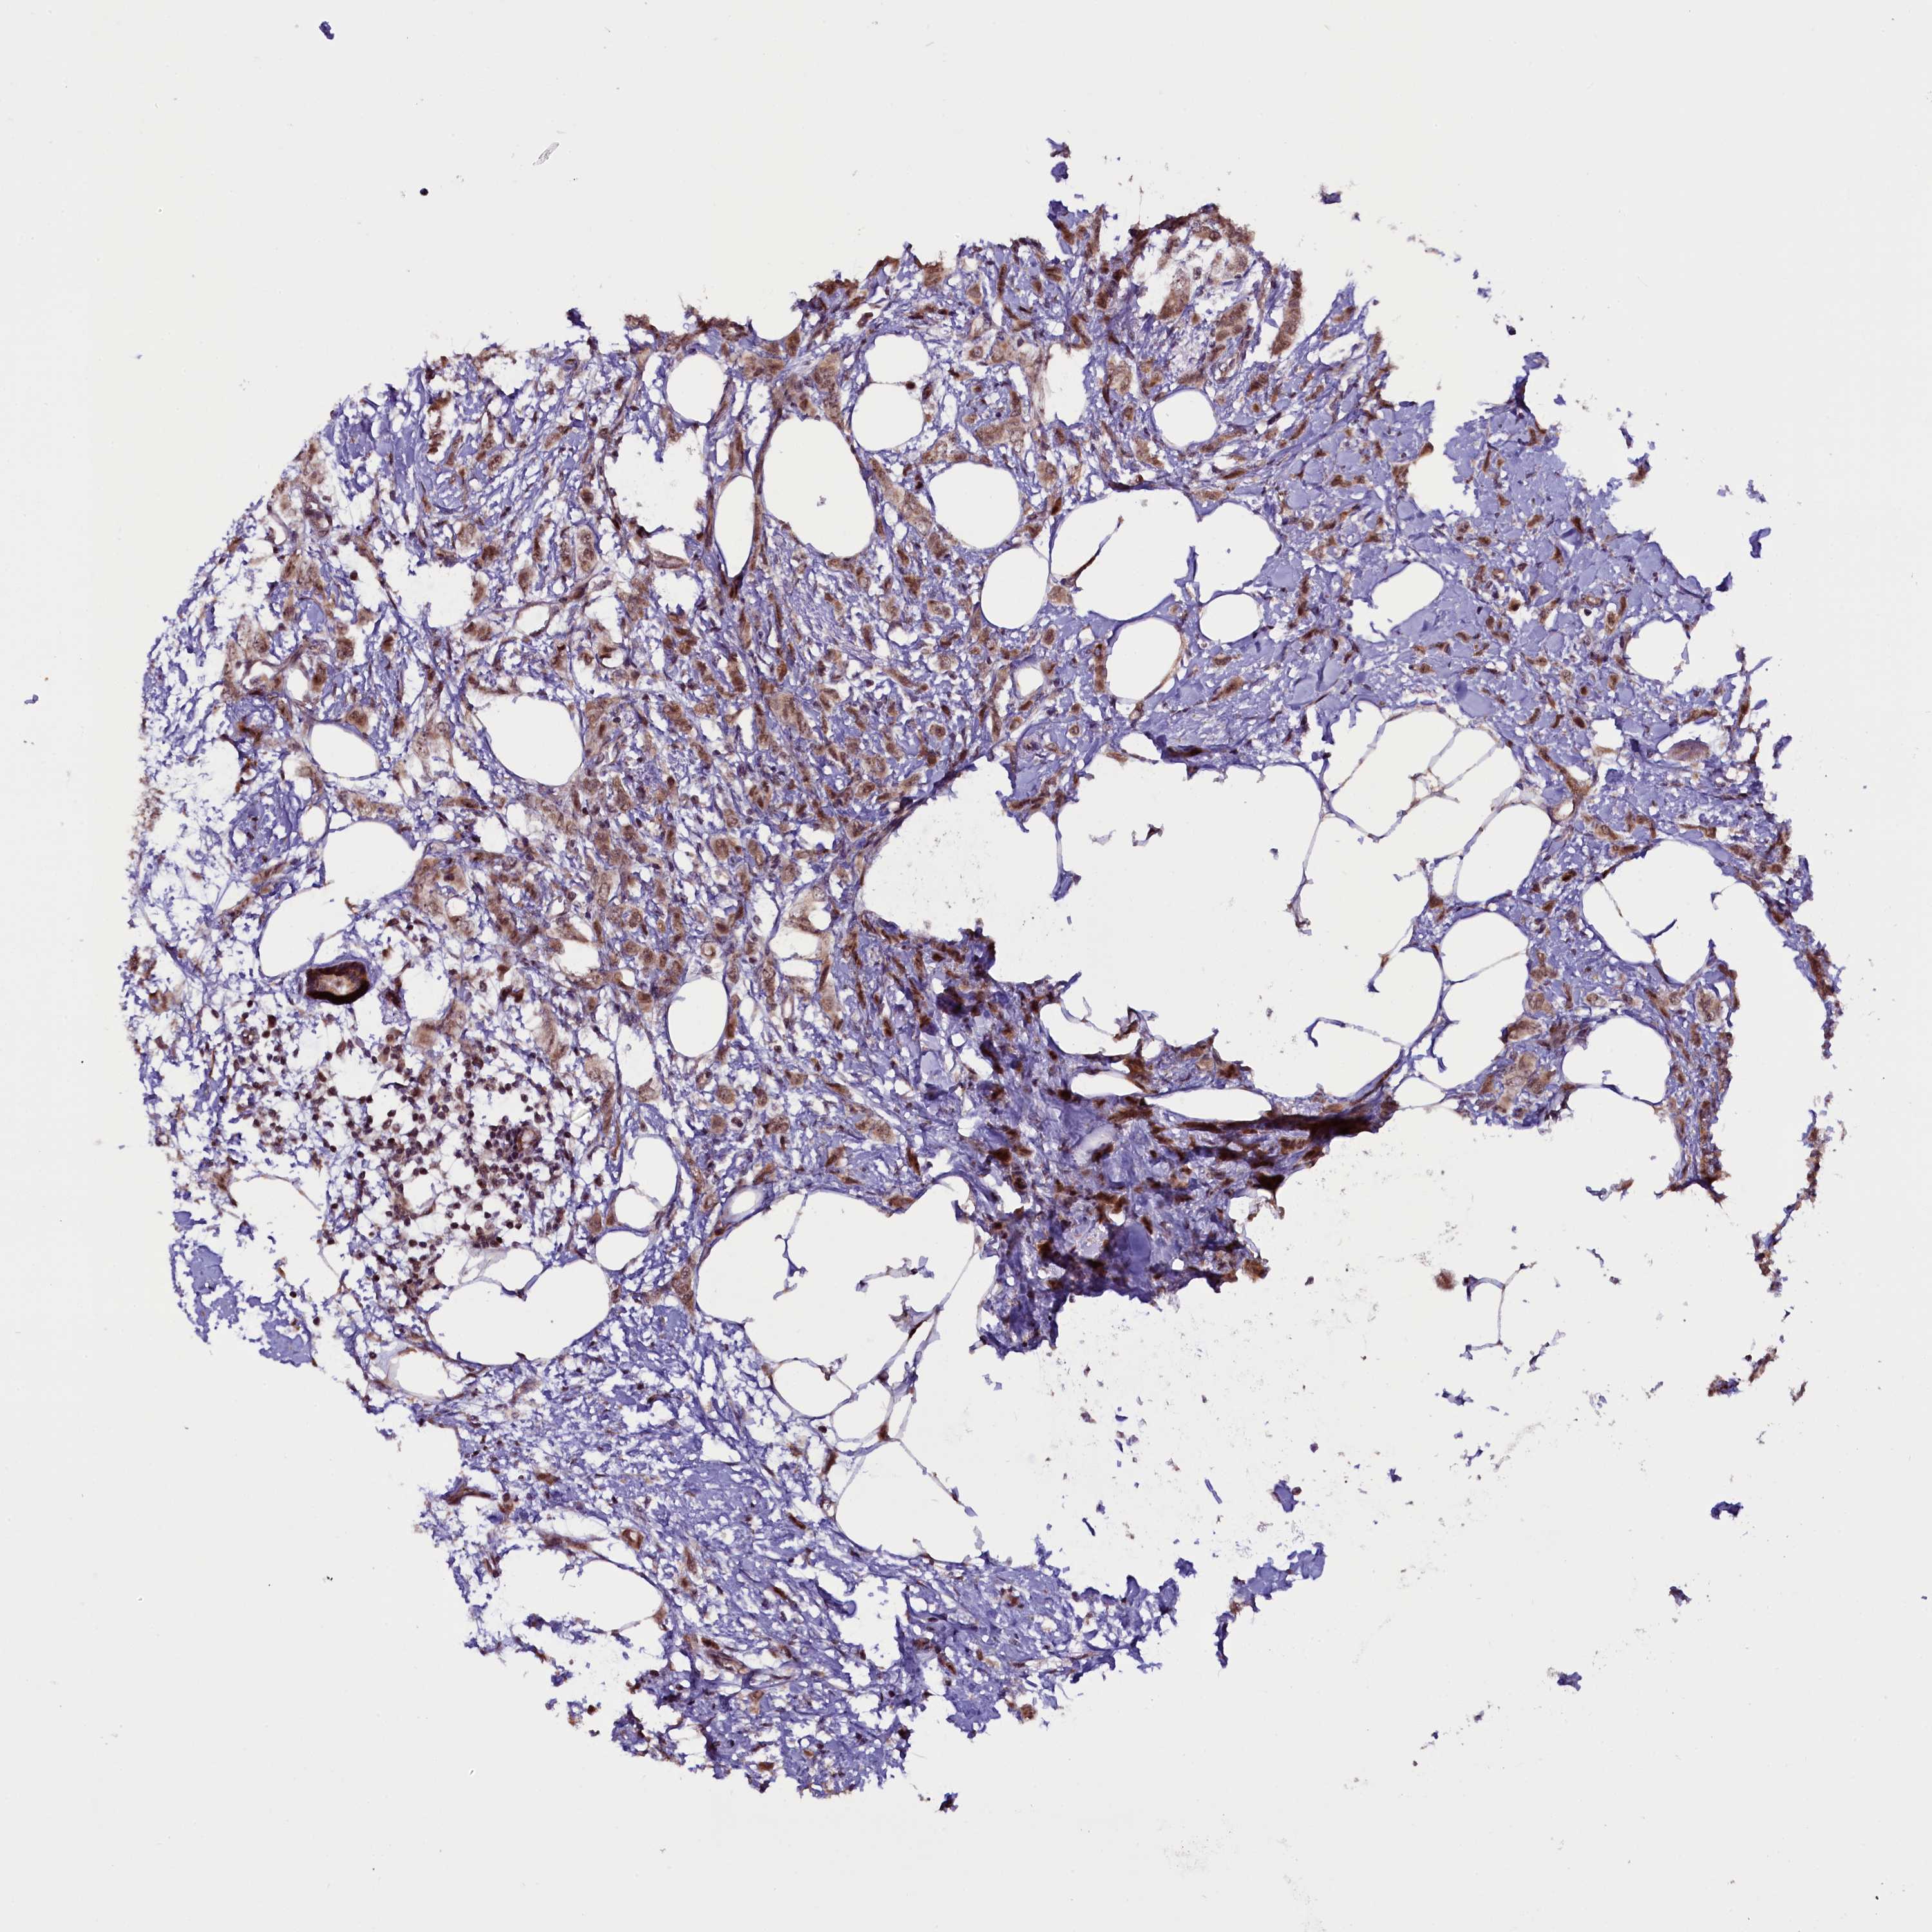

CANCER BREAST CANCER Show tissue menu

BRCA TCGA BRCA VALIDATION PROTEIN EXPRESSION

Breast cancer

Human cancer